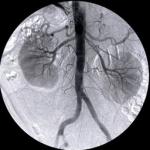

U Srbiji je godišnje potrebno između 400 i 500 transplantacija bubrega, a od 1975. godine od kad se taj organ presađuje izvršeno je 1.250 operacija, rečeno je na konferenciji za novinare povodom obeležavanja Dana davalaca organa.

Državna sekretarka Ministarstva zdravlja Nevena Karanović navela je da je u Srbiji godišnje potrebno između 100 i 150 transplantacija jetre i 20 do 30 tran...